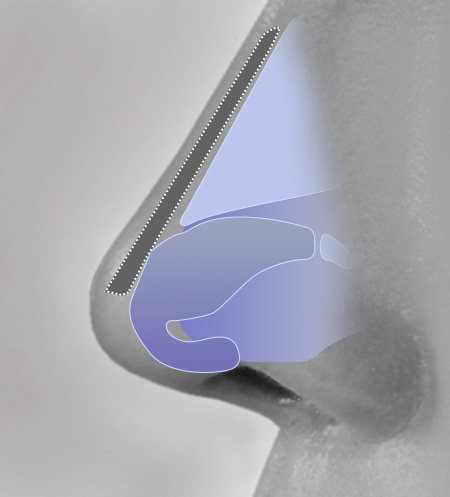

This is 1:1 customized rhinoplasty that allows you to create the most suitable implant for your nose by using 3D printer to create the patient’s skeleton, cartilage, skin tissue, and muscle with data obtained from 3D-ct images.

Because it is possible to manufacture a customized implant that fits perfectly to the nasal bone, it is safe and there is little worry about reoperation as it significantly reduces side effects such as bending, silicone seepage, and lifting.

1Check current status

We proceed with 3D-CT imaging to closely analyze the current condition.

2Design and Prediction

We design a nose shape that suits the current state through software.

4Custom Nose Implant

A custom-designed, custom-made nose implant for patients is made with a 3D printer.

Current Status

Virtual results after design